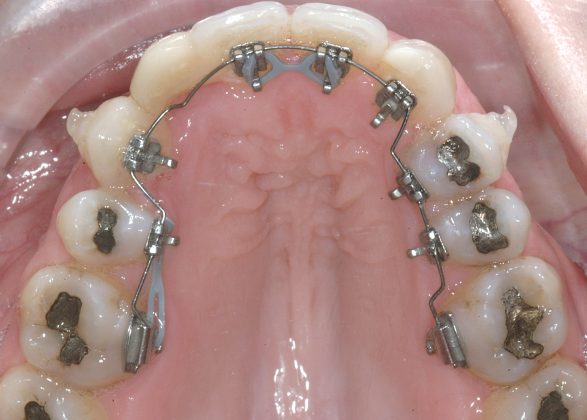

Il protocollo terapeutico ha previsto l’estrazione del primo premolare inferiore sinistro (3.4) e del primo superiore destro (1.4), l’applicazione di una apparecchiatura fissa linguale 2D e di una meccanica asimmetrica di ancoraggio e movimento ortodontico a entrambe le arcate (Figure 3a-b).

Il trattamento è iniziato con l’estrazione dei due premolari in unica seduta in anestesia locale e l’applicazione simultanea, dopo una settimana, della apparecchiatura linguale inferiore e superiore, non essendoci problemi di overbite e potenziali interferenze in occlusione tra l’apparecchiatura superiore e i frontali inferiori. All’arcata superiore è stata effettuata una iniziale chiusura dello spazio estrattivo con forze molto leggere in ancoraggio medio su arco .014” Nichel-Titanio e successivamente .016” Nichel-Titanio, bondato in prima fase per maggior stabilità direttamente sulla superficie mesiale di 2.4.

Nota tecnica: il movimento iniziale di distalizzazione della corona di 1.3 mediante tipping distale (vista la posizione radicolare iniziale) è stato ottenuto con una catenella elastica leggera inserita su 1.6, 1.5 e ancorata su 1.3, abbracciando per maggior controllo l’aletta disto-occlusale e quella gengivale del bracket linguale.

Per la chiusura dello spazio all’arcata inferiore, dopo la preliminare fase di allineamento e livellamento2, con la stessa sequenza iniziale di archi (.014” e poi .016” Nichel-Titanio), è stato temporaneamente applicato un sistema di ancoraggio ausiliario vestibolare, mediante fibre rinforzate, bondate sulla superficie vestibolare di 3.5, 3.6, 3.7 (Figura 4).